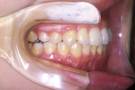

治療前

治療後

小臼歯は抜歯せずに、知歯を抜歯して治療しました。

①主訴 前歯の前突 ②診断名 上顎前突 ③年齢 18歳 ④使用装置 エッジワイズ装置 ⑤抜歯部位 下あご左右知歯 ⑥治療期間 約1年半 ⑦治療費概算 90万円